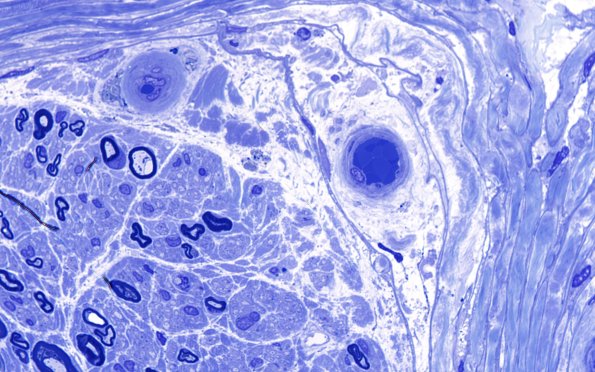

Hypoxia-Ischemia, fetal-neonatal

14A1 (Case 14) Plastic 100X 1